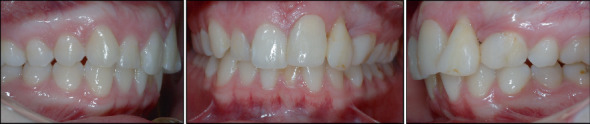

In this case report, we present the treatment of an adult patient who had experienced dental trauma resulting in the loss of one tooth and damage to two others. The patient was referred to our clinic 4 years after the accident, where a comprehensive examination revealed external root resorption and loss of supporting tissue. To address the patient's concerns, we developed an interdisciplinary treatment plan, which included orthodontic treatment to level the curve of Spee, reduce the deep bite, and extrude the affected teeth. After that, we extracted the damaged Teeth 2.1 and 2.2 due to their poor prognosis and replaced them with autotransplantation of Teeth 1.4 and 3.1. Before the procedure, both teeth underwent endodontic treatment, and 6 weeks later, they were built up to aesthetically and functionally replace the lost teeth. Additionally, postautotransplantation orthodontic treatment was conducted to close the donor site space and bring the autotransplanted teeth to an ideal position. The interdisciplinary approach and successful treatment of this case suggest that autotransplantation can be a valid option for restoring compromised teeth, especially in adult patients who require orthodontic treatment. In conclusion, autotransplantation offers multiple benefits, including preserving the natural dentition, avoiding the use of dental implants or prostheses, and achieving excellent aesthetic and functional results. Furthermore, this case underscores the importance of individualized treatment planning and collaboration among dental specialists to achieve optimal outcomes for patients.

Abstract Image